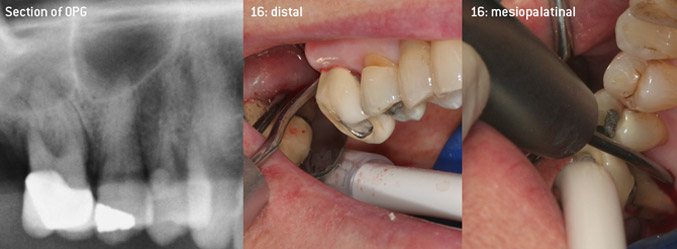

Come pionieri dello sviluppo della nuova punta per ablatori 3AP diamantata, i due dentisti hanno riconosciuto la necessità di migliorare le restrizioni di manipolazione delle punte diamantate disponibili in commercio, specialmente durante il trattamento della forcazione e lavorando su tasche intraossee strette. Tutto ciò deve essere fattibile sia per procedure non chirurgiche (figura 2) sia per procedure chirurgiche (figura 3).

L'idea era di sviluppare una punta applicabile universale al fine di evitare le sostituzioni della punta, per cui era richiesto parecchio tempo. Inoltre, si doveva facilitare l'utilizzo delle nuove punte in tasche intraossee strette dalla parte distale e all'entrata della forcazione distale dei molari mascellari, per consentire così un utilizzo più efficace degli strumenti. Ciò è stato possibile adottando una curva dello strumento con un diametro più ampio (figura 1), un vantaggio enorme in particolare per il debridement chiuso sui denti con perdita avanzata degli attacchi e dove entra in gioco la forcazione (figura 4).